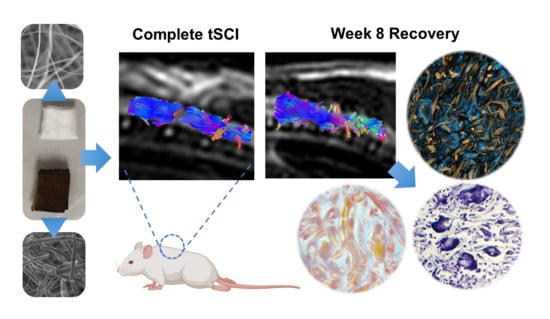

3.1. Scaffold Design and Rapid Tissue Response to Plasma-Modified Scaffolds

3.2. Implanted Animals Showed Improved Motor Recovery

3.3. Scaffolds Promoted Tissue Growth at the Injury Site

3.4. Recovery of Structural Damage by the Fibrillar Scaffolds